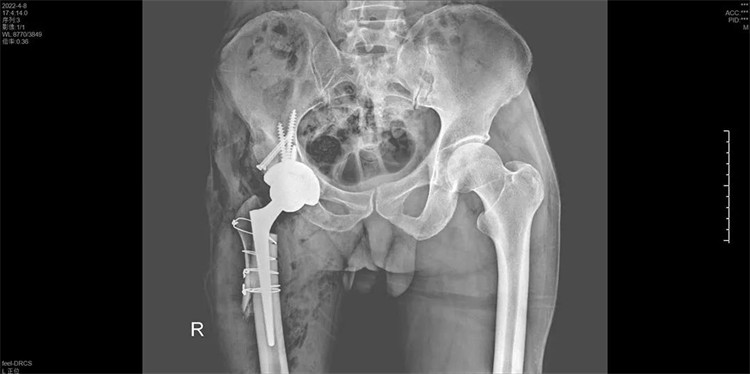

手術(shù)過(guò)程一氣呵成,手術(shù)歷時(shí)2個(gè)小時(shí),出血200ML,順利地為周大伯進(jìn)行了右側(cè)人工全髖關(guān)節(jié)置換術(shù),將人工髖關(guān)節(jié)準(zhǔn)確地安裝在周大伯的真臼內(nèi)并做了牢固的固定。術(shù)后第1天周大伯就已下地行走。

術(shù)后第一天下地走路